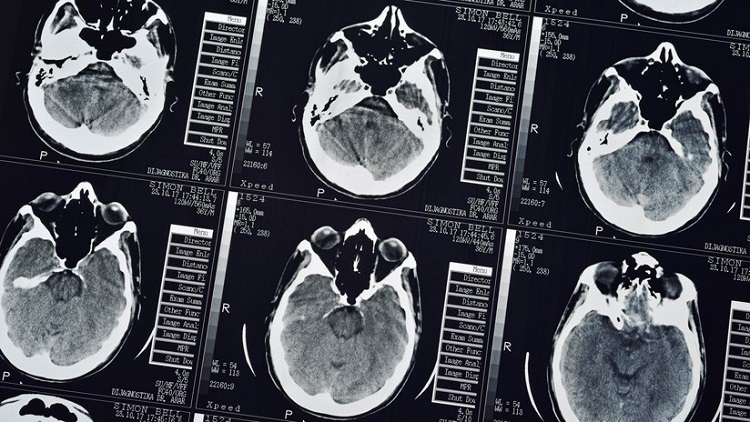

El médico encontró que más de 700 tenias, que el paciente albergó en su cerebro, pecho y pulmones, ya habían causado daños a sus órganos. «Hay múltiples presencias de lesiones que ocupan espacio en el cerebro del paciente. También están en los pulmones y llenan los músculos dentro de la cavidad torácica», señaló Wang.